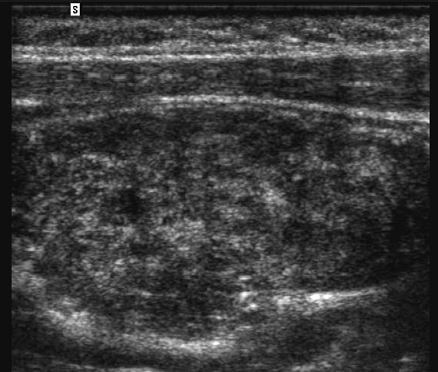

Focal testicular atrophy

• Focal hypoechoic striations and bandlike regions radiating from the periphery of the testis toward the mediastinum.

• Due to focal tubular atrophy and fibrosis